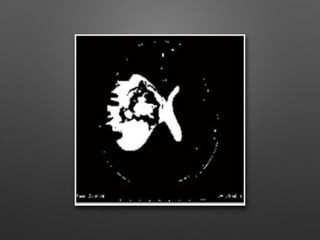

(a) Threshold image (b) Image showing connected

regions

(a) Threshold image(b) Image showing connected regions